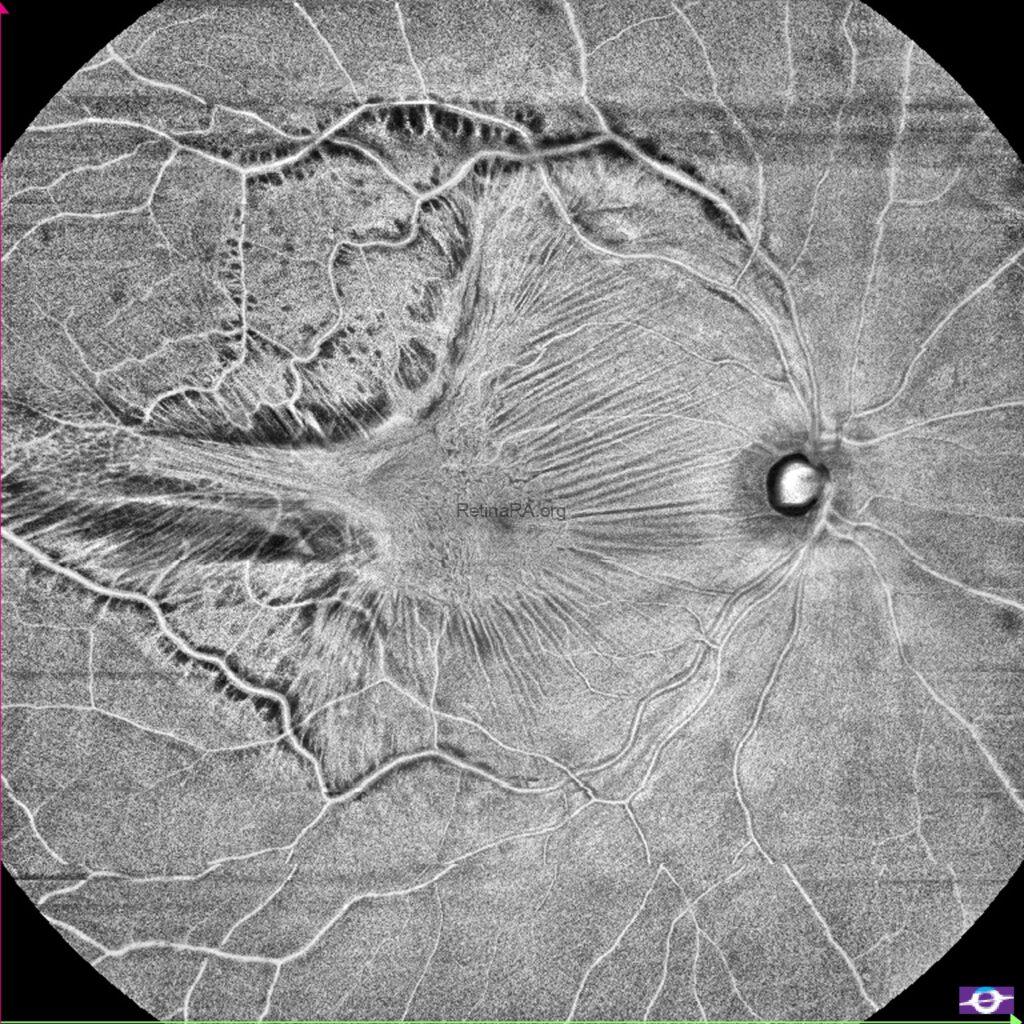

As seen in the color fundus photograph, there was significant tangential macular traction, particularly at the temporal side. Enface OCT demonstrated this remarkably well. It clearly showed the contraction of the epiretinal membrane, distortion of the retina, and traction-related retinal damage.

B-scan OCT shows us the loss of foveal depression due to ERM. In the upper scan, the posterior hyaloid appears attached to the optic disc. The lower OCT scan shows that, the posterior hyaloid remains attached to the retina in the temporal macular region where the retinoschisis appearance and damaged retina were present.

In the upper OCT, marked thinning of the temporal retina was visible. Disruptions were observed especially within the retinal nerve fiber layer and the ganglion cell layer.